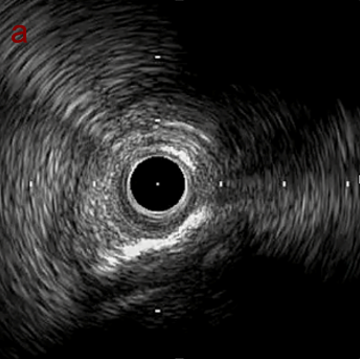

IVUS after OAS high speed 3回

IVUS imaging after high speed 3回

a,b,cはさらに石灰化に食い込み、石灰化量は減少。

それに伴いdではbiasがさらにtentingのIVUS所見にへんかしhigh injury riskと思われた。